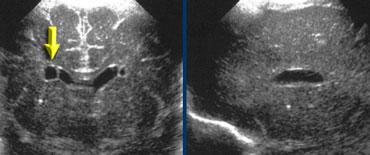

TRÁI: Mặt cắt đứng ngang, mũi tên xanh lá chỉ xuất huyết độ 3. PHẢI: Mặt cắt đứng dọc, mũi tên vàng chỉ nhồi máu tĩnh mạch.

Xuất huyết nội sọ độ 3

Hình bên trái là xuất huyết nội sọ độ 3 lấp đầy não thất bên trái.

Cũng lưu ý vùng tăng âm hình nêm ở phía trên-bên của não thất.

Đây là hình ảnh của một ổ nhồi máu tĩnh mạch nhỏ.

Cùng bệnh nhân như trên.

Hai tuần sau, ổ nhồi máu tĩnh mạch đã tiến triển thành vùng giảm âm với sự hình thành nang.